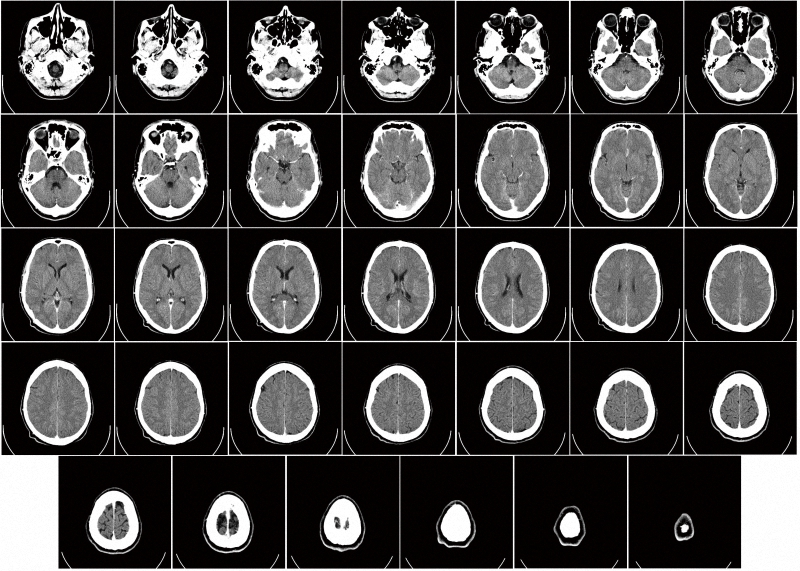

CT辐射最高 胸透基本取消

在我们日常能接触到的放射性检查中,CT(计算机断层扫描)类成像的辐射剂量最高。CT是一种三维放射线医学影像,主要通过单一轴面的X射线旋转照射人体。由于不同的组织对X射线的吸收(阻挡)能力不同,可以用电脑的三维技术重建出断层面影像,将所有断层影像层层堆叠,就形成了立体影像。这种技术优点在于影像分辨率高,可以全面而完整地视察到患处的情况,但也带来了不容忽视的受照剂量,个个都是“毫希级”的。一次盆腔CT带给人体的有效剂量达20毫希,心血管CT为9~12毫希、结肠镜CT为6~11毫希、胸部CT为7~8毫希、头部CT为1~2毫希。除了头部CT外,其他都已经明显超出了一年的平均剂量。

一次脑部CT成像大约贡献1~2毫希辐射